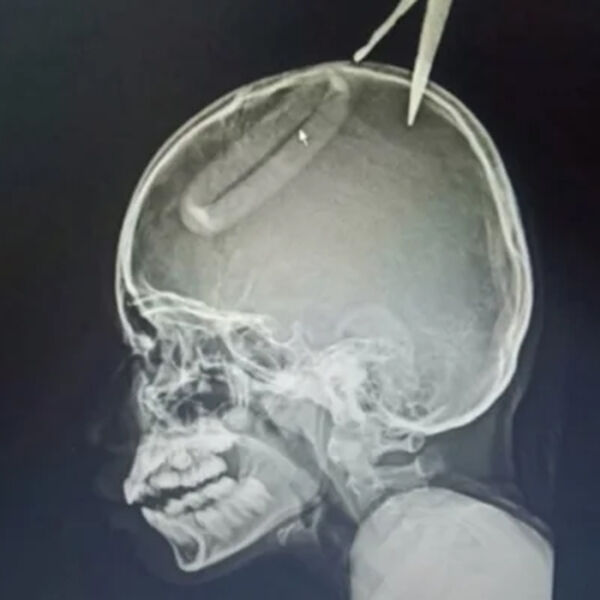

Одно из лезвий воткнулось в голову девочки, на помощь ей пришел дедушка, который находился в доме, пенсионер не смог самостоятельно вытащить ножницы из головы внучки.

Пострадавшую госпитализировали, врачи установили, что ножницы погрузились в череп на два с половиной сантиметра и едва не задели нерв. Несколько дней девочка провела в больнице и была выписана на амбулаторное лечение.